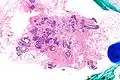

| Very low magnification micrograph of atypical ductal hyperplasia (ADH). The piece with ADH was circled by the pathologist with a marker, as it is so small, and sent for an additional opinion. H&E stain. | |